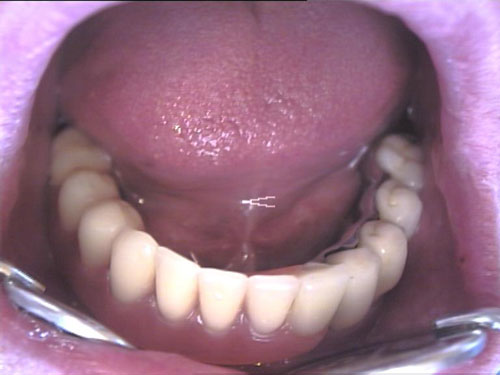

Keramikkrone 1

Keramikkrone 2